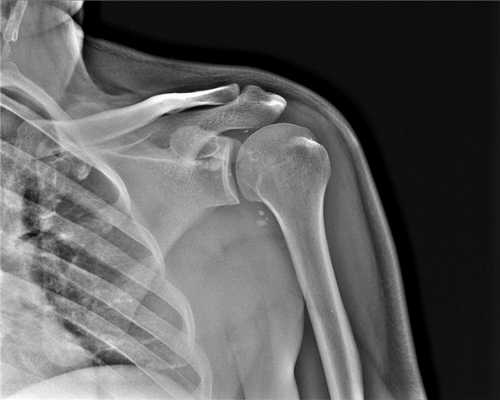

Когда КТ плечевого сустава лучше, чем МРТ плеча

Компьютерное рентгеновское исследование плеча больше рекомендовано при проведении диагностики костной составляющей человеческого организма, а именно: травматических повреждений костей плеча человека; неправильно сросшиеся кости, наличие костных шпор; поражений костей опухолевой природы как первичных, так и вторичных; атеросклеротических изменений сосудов.

Противопоказаниями для проведения МСКТ могут являться беременность и кормление ребенка грудью. Также метод компьютерной томографии не рекомендован маленьким детям без серьезных медицинских показаний из-за лучевой нагрузки.